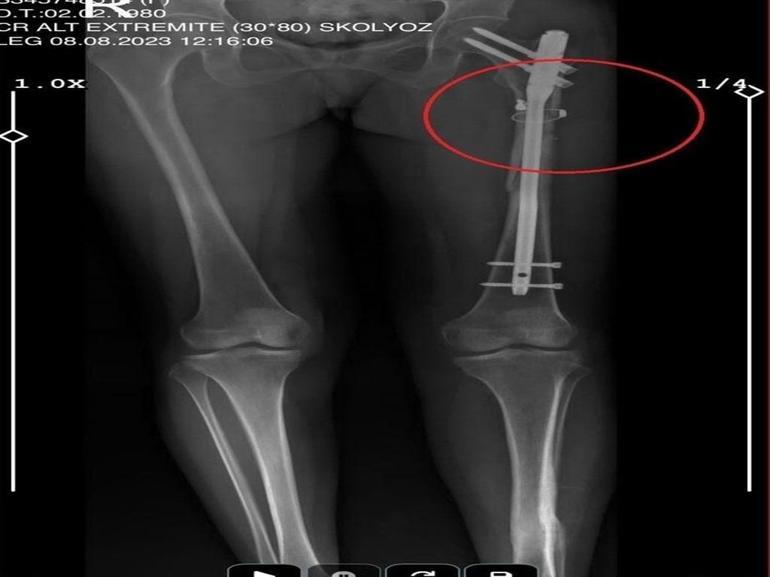

İlyas Sarıkaya, sevgilisi Fatma O.'yu da 8 kurşunla vurup, yaraladı. Arkadaşı Özaslan'ın cesedini önce çarşafa sonra da streç filme sarıp bantlayan Sarıkaya, eczaneden aldığı sargı bezi ve ilaçlarla pansumanını yaptığı sevgilisine yaralı haldeyken 21 gün boyunca cinsel saldırıda bulundu.

Fatma O., annesine yazdığı mesajda, “Odada ceset var. Telefon dinleniyor. Bana 8 el ateş etti. Yaralıyım. Polisi görürse önce beni öldürecek. Onu parayla kandırıp, evden çıkartın. Sonra da beni alın” dedi. Fatma O.’nun annesi, bu mesaj sonrası polise gidip şikayette bulundu. Polis, Fatma O.'nun annesi aracılığıyla Sarıkaya ile iletişime geçti. Fatma O.'nun annesi, telefonla aradığı Sarıkaya'yı, kızına para götürmesi için evine çağırdı. Ekipler, parayı almaya gelen Sarıkaya'yı kendilerine silah çekmesine rağmen yakaladı. Eve giden ekipler, ağır yaralı haldeki Fatma O. ve kokmaya başlayan cesetle karşılaştı. Emniyetteki işlemlerin ardından Sarıkaya tutuklanıp, hakkında dava açıldı.